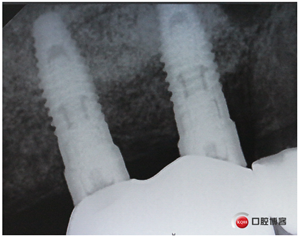

同期植入植體。

再看看片子。